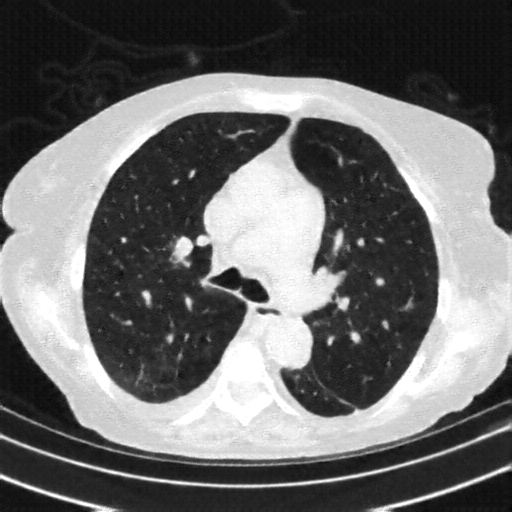

Original NATIVE CT scan (input)

Full window (WL 1023.5, WW 4095 β†’ Low βˆ’1024, High +3071)

Lung window (WL -600, WW 1500 β†’ Low βˆ’1350, High +150)

Mediastinum window (WL 40, WW 400 β†’ Low βˆ’160, High +240)